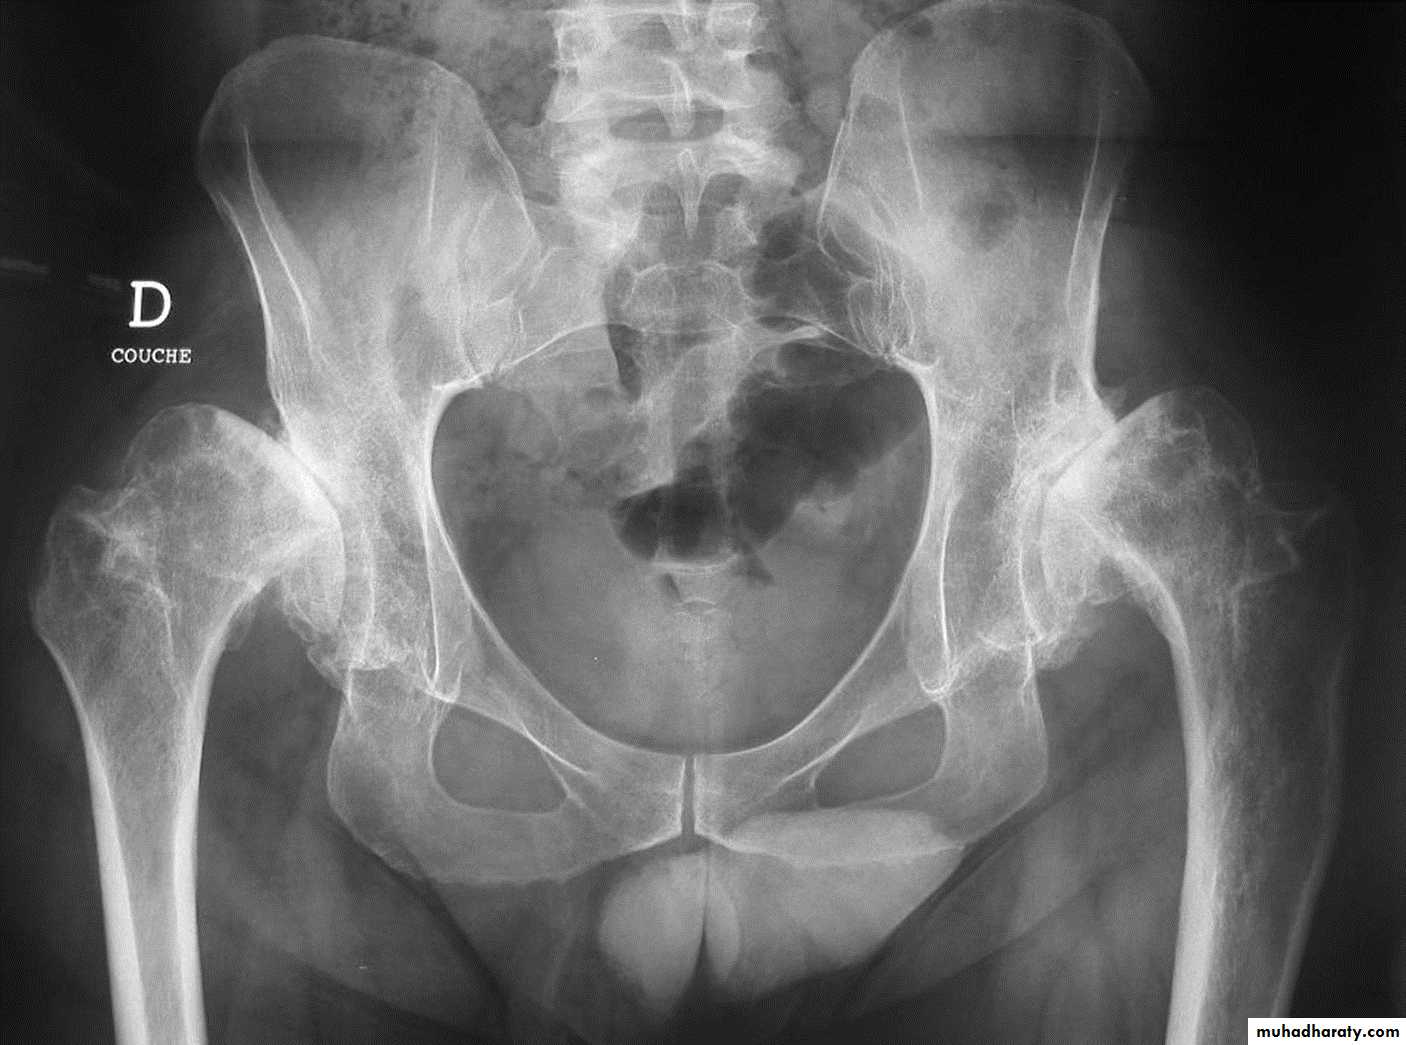

ANKYLOSING SPONDYLITIS (AS)

Seronegative spondyloarthropathy of the axial skeleton and proximal large joints.

Clinical: males >> females. HLA-B27 in 95%. Insiduous onset of back pain and stiffness. Onset: 20 years.Radiographic features:

* SI joint is the initial site of involvement:

bilateral, symmetrical

Erosions: early ,Sclerosis: intermediate , ankylosis: late

* Contiguous thoracolumbar involvement

Vertebral body "squaring": early osteitis

* Syndesmophytes

* Bamboo spine: late fusion and Bamboo spine

ligamentous ossification

*ankylosed spine (fracture)

* Enthesopathy is common(("whiskering of tuberosities )

* Arthritis of proximal joints (hip > shoulder) in 50% ,erosions and osteophytes